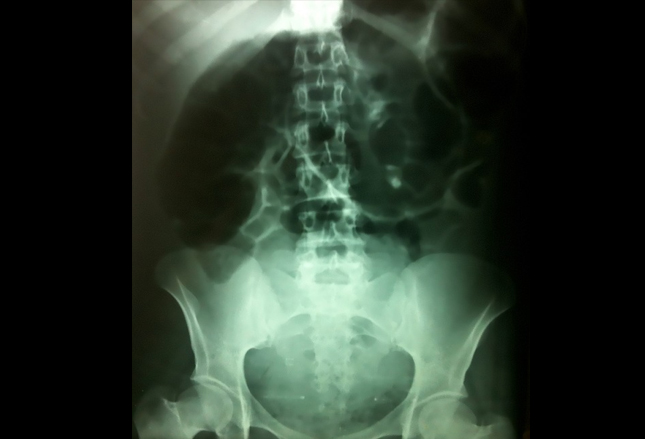

,因“痉挛性”腹痛1天,由疗养院转至医院。中度疼痛,主要位于左下腹。患者自述感觉胃部比平时更加“臃肿”。长期便秘

;入院前最后一次大便是2天前。体格检查,生命体征正常,脐周触诊有中度压痛,无腹壁紧张和反跳痛。直肠检查没有发现粪便。胸部X光如图,最可能的诊断是什么?

答案:D.乙状结肠扭转

通过CT检查

,可以看见近端结肠正常表现,乙状结肠扩张(如下图箭头所示)。长期卧床患者和精神障碍患者的风险最大,因为精神药物可以减缓肠道蠕动。冗余乙状结肠(乙状结肠延伸,导致一个冗余环路)也是风险因素。患者一般表现为急性腹痛

、痉挛、腹胀和便秘。